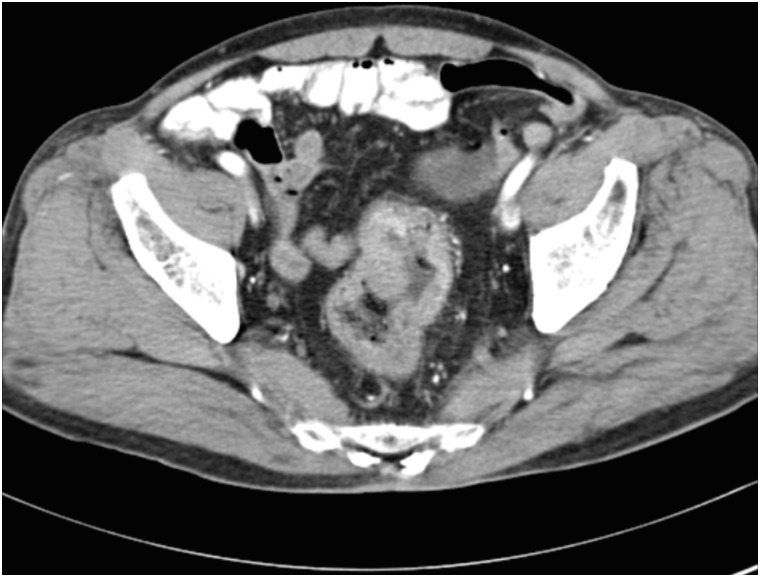

A 71-year-old male patient was diagnosed with rectal cancer on July 31, 2003. The results of his abdominal CT scans performed at a university hospital earlier in the same month demonstrated rectal wall thickening, wall enhancement, and masses protruding into the rectal lumen (Fig. 3). On August 18, 2003, he underwent surgery for the removal of the rectal cancer. His final diagnosis was that of rectal tubular adenocarcinoma, Borrmann type II. The patient had diabetes and hypertension, and was diagnosed with pneumoconiosis in 2004, based on the results of a chest CT scan, which was performed to investigate his breathing difficulty, coughing, and sputum production. Owing to varying statements in his medical records, his smoking history could only be estimated to have ranged between 2.5 and 25 pack-years. He admitted to drinking alcohol 2–3 times per week and had stopped drinking since 2000. There was no family history of cancer. Patient B was also a day laborer; hence we reviewed his employment insurance records and NTS tax reports as well as his own statements, to summarize his job history. From 1954 to 1975 (about 21 years), the patient worked at shipbuilding and repair workplaces. He then worked at ship repair yards for approximately 28 years (1975–2003). While at work, he laid pipes in ships, installed asbestos insulation on pipes and outer walls of frozen storage vessels, performed surface cleaning and preparation for painting (i.e., grinding or abrasive machining and sandblasting), and executed ship interior repairs.

Fig. 3

Patient B: abdominal computed tomography images. The rectal wall exhibits abnormal thickening and enhancement with protruding masses in the rectal lumen.